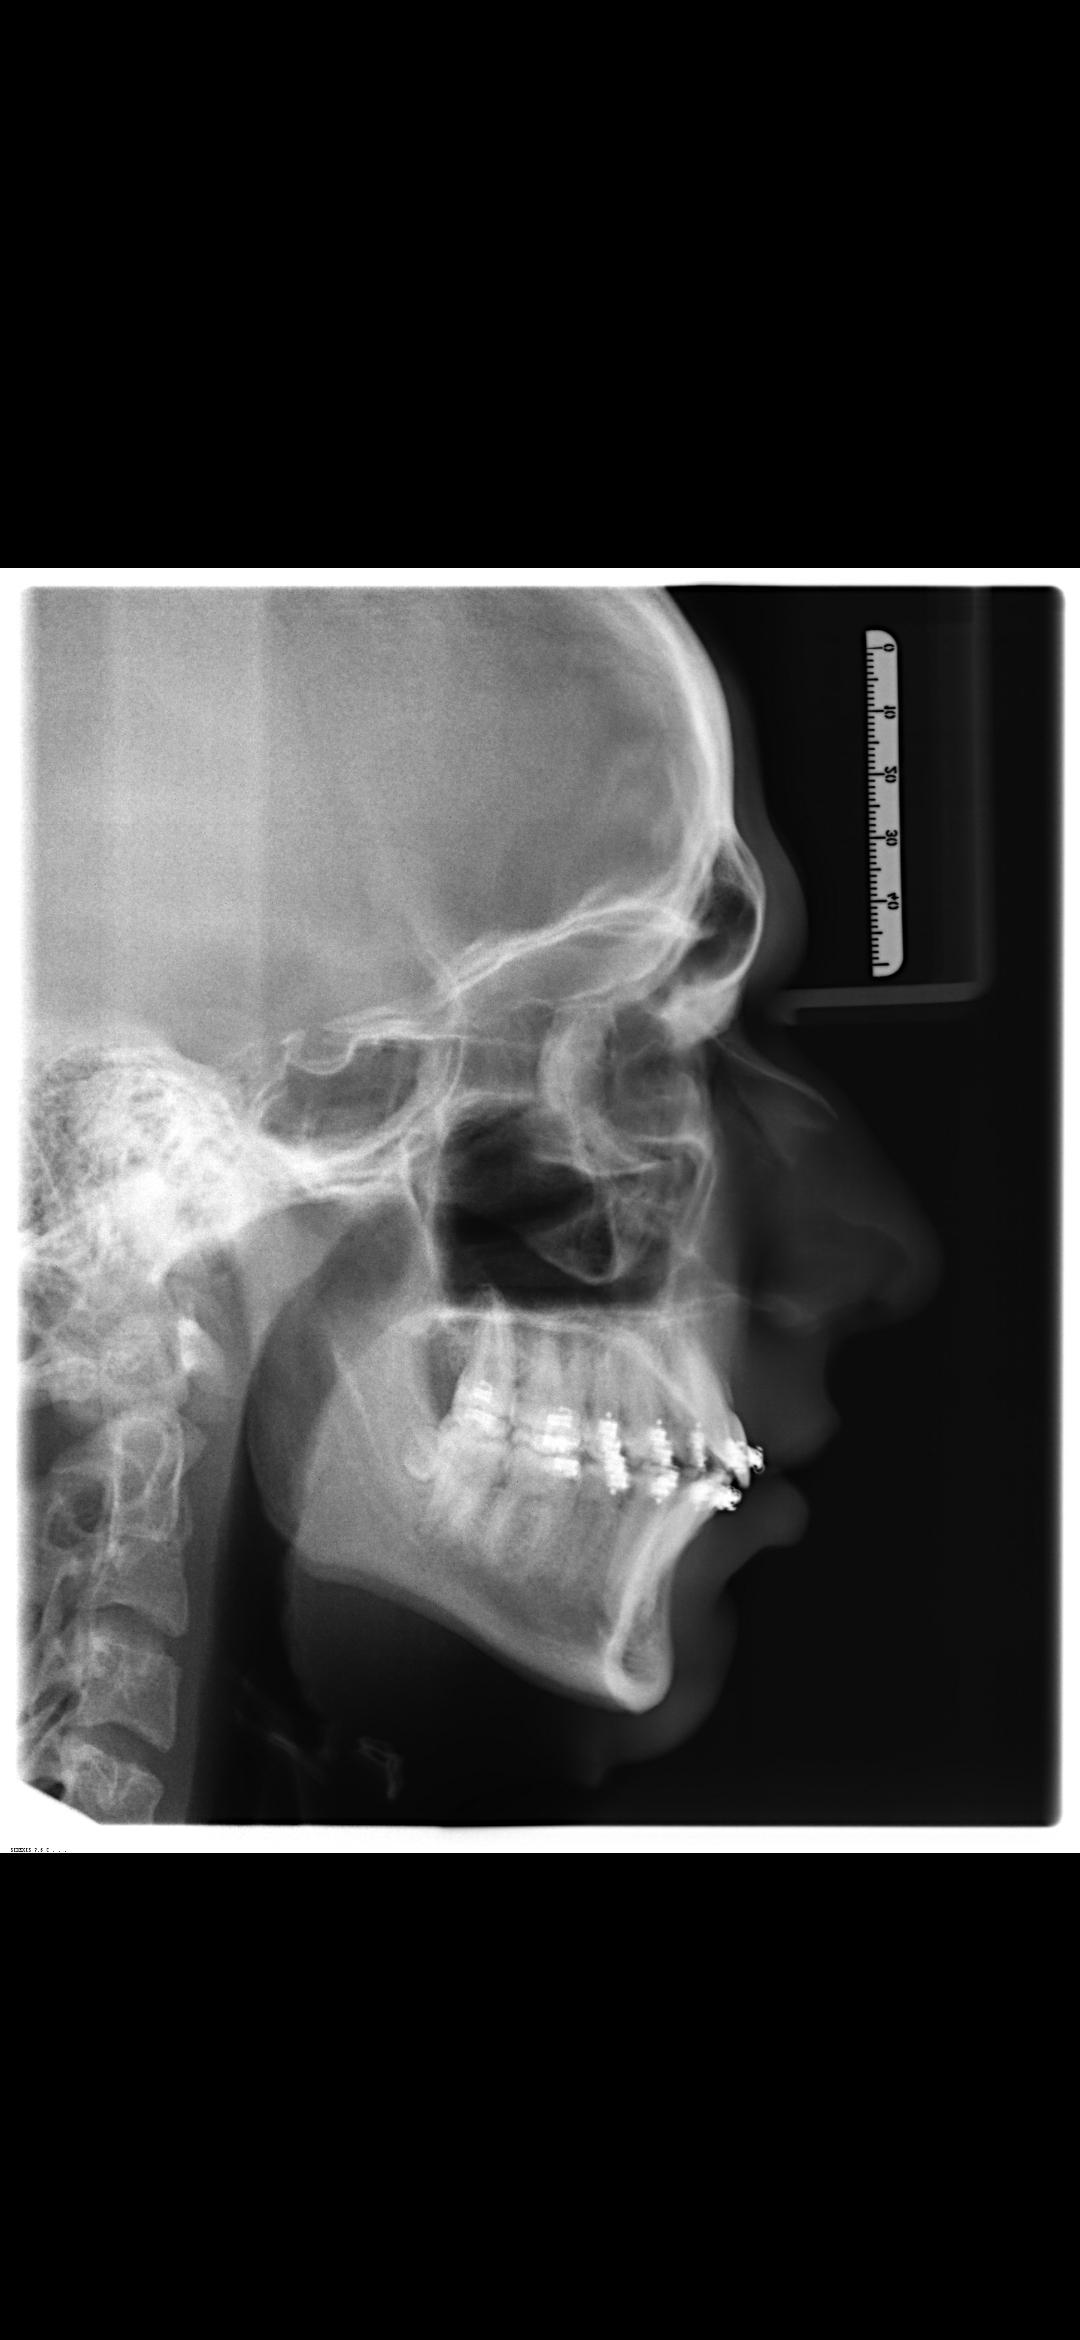

I have a sub 3 side, and a MTN front, my chin is very recessed and both my mandible and my maxilla are too short.